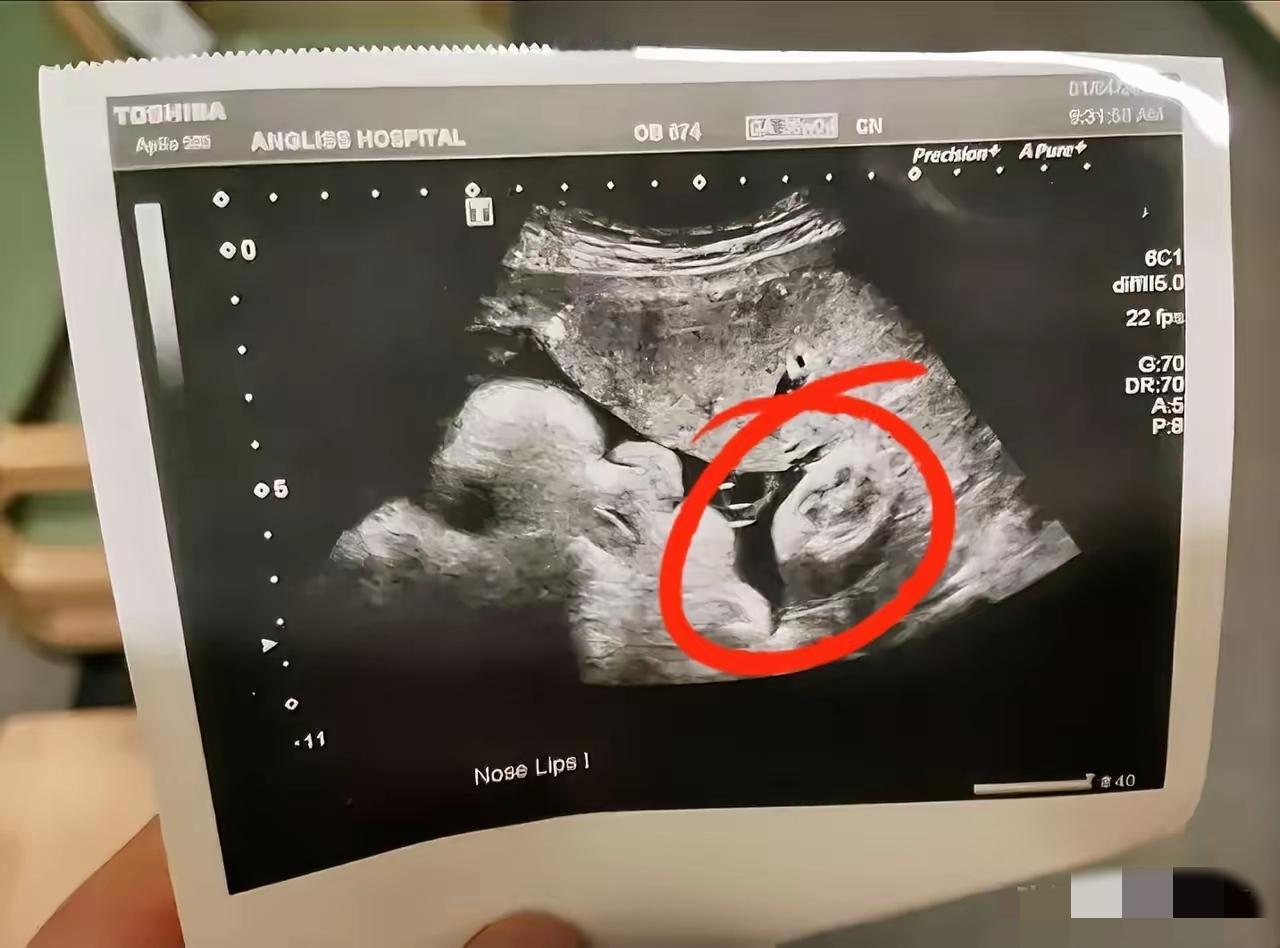

“我肚子疼,快帮我看看”16岁女孩和家长匆匆赶到医院,没想到医生询问“你是不是怀孕了?”女孩坚定摇头“没有”结果B超一看,女孩已经怀孕了,而且孩子在盆腔内,肚子疼是宫缩引起的! 现代孩子性观念非常开放,不同于以前的保守,强调性教育的重要性,尤其是有女孩的家庭更要重视! 麻烦看官老爷们右上角点击一下“关注”,既方便您进行讨论和分享,又能给您带来不一样的参与感,感谢您的支持!